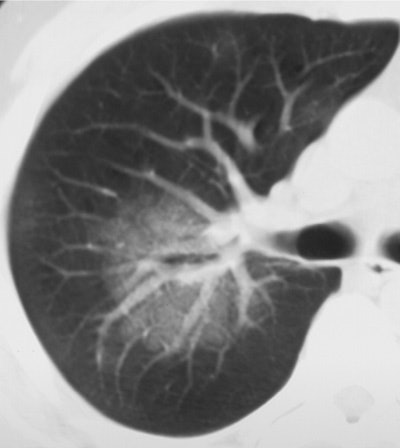

| Above (Fig. 2a), transverse conventional CT scan in 33-year-old man with SARS (obtained at day 4 after admission) shows ground-glass opacification. Below (Fig. 2b) follow-up thin-section CT scan (obtained at day 46 after admission, 29 days since discharge) of the corresponding area shows evidence of fibrosis, such as parenchymal bands, irregular interface, and traction bronchiectasis. Images and captions from Radiology Online, June 12, 2003, republished by permission of the author and the Radiological Society of North America, © RSNA 2003. |